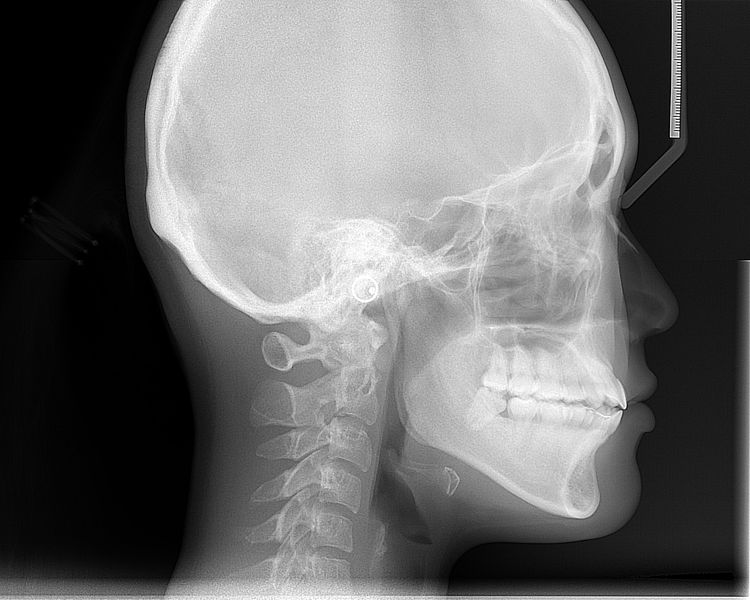

Jak spravit poškozenou lebku? Napěstováním kmenových buněk!